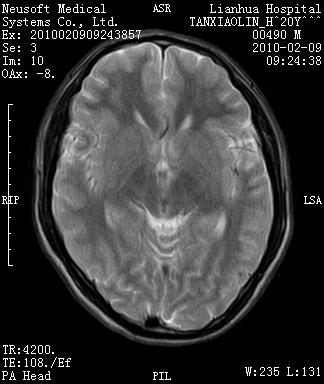

20岁男性患者,平时偶有头痛而无其他不适,现因持续头痛服药后无缓解而来院就诊。

松果体囊肿?

松果体区占位继发轻度脑积水?该患者有ct资料,我已发上。

考虑松果体囊肿。